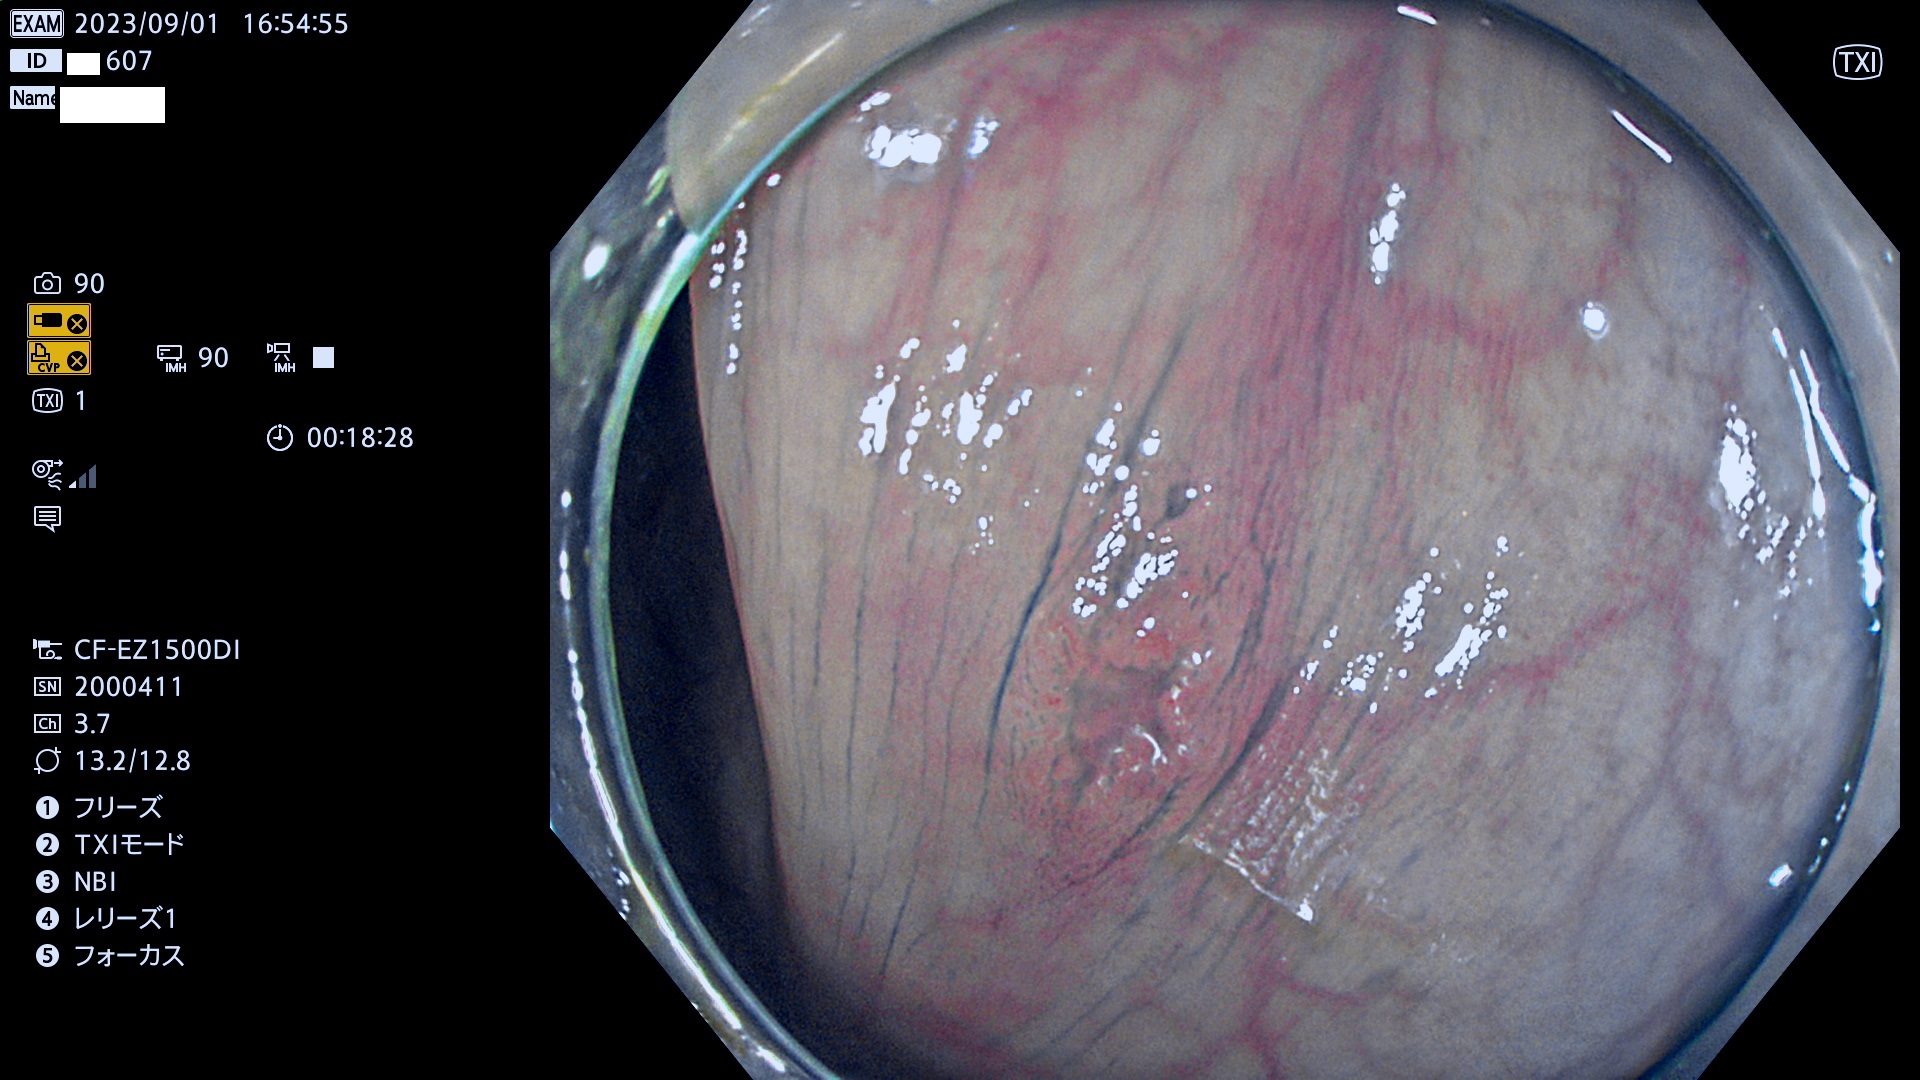

表面型腺腫(Flat Adenoma)の中で、完全に平坦な物をUb、陥凹している物をUcと呼びます。平坦隆起型(Ua)よりも、発見が難しく危険な病変です。このタイプは「内視鏡後・大腸癌の重要犯人」であり、この発見率は「腺腫発見率」よりも、重要な意味があります。

毎週の検査(木・金・土・日)に発見されたUb、Uc型・腺腫を、その週の日曜の夜にUPし1週間、提示します。

抽出の対象期間 2023年8月31日(木)〜9月3(日)の4日間(48件の検査)12件